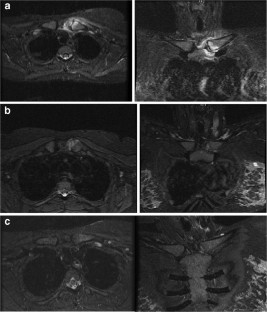

Fig. 2